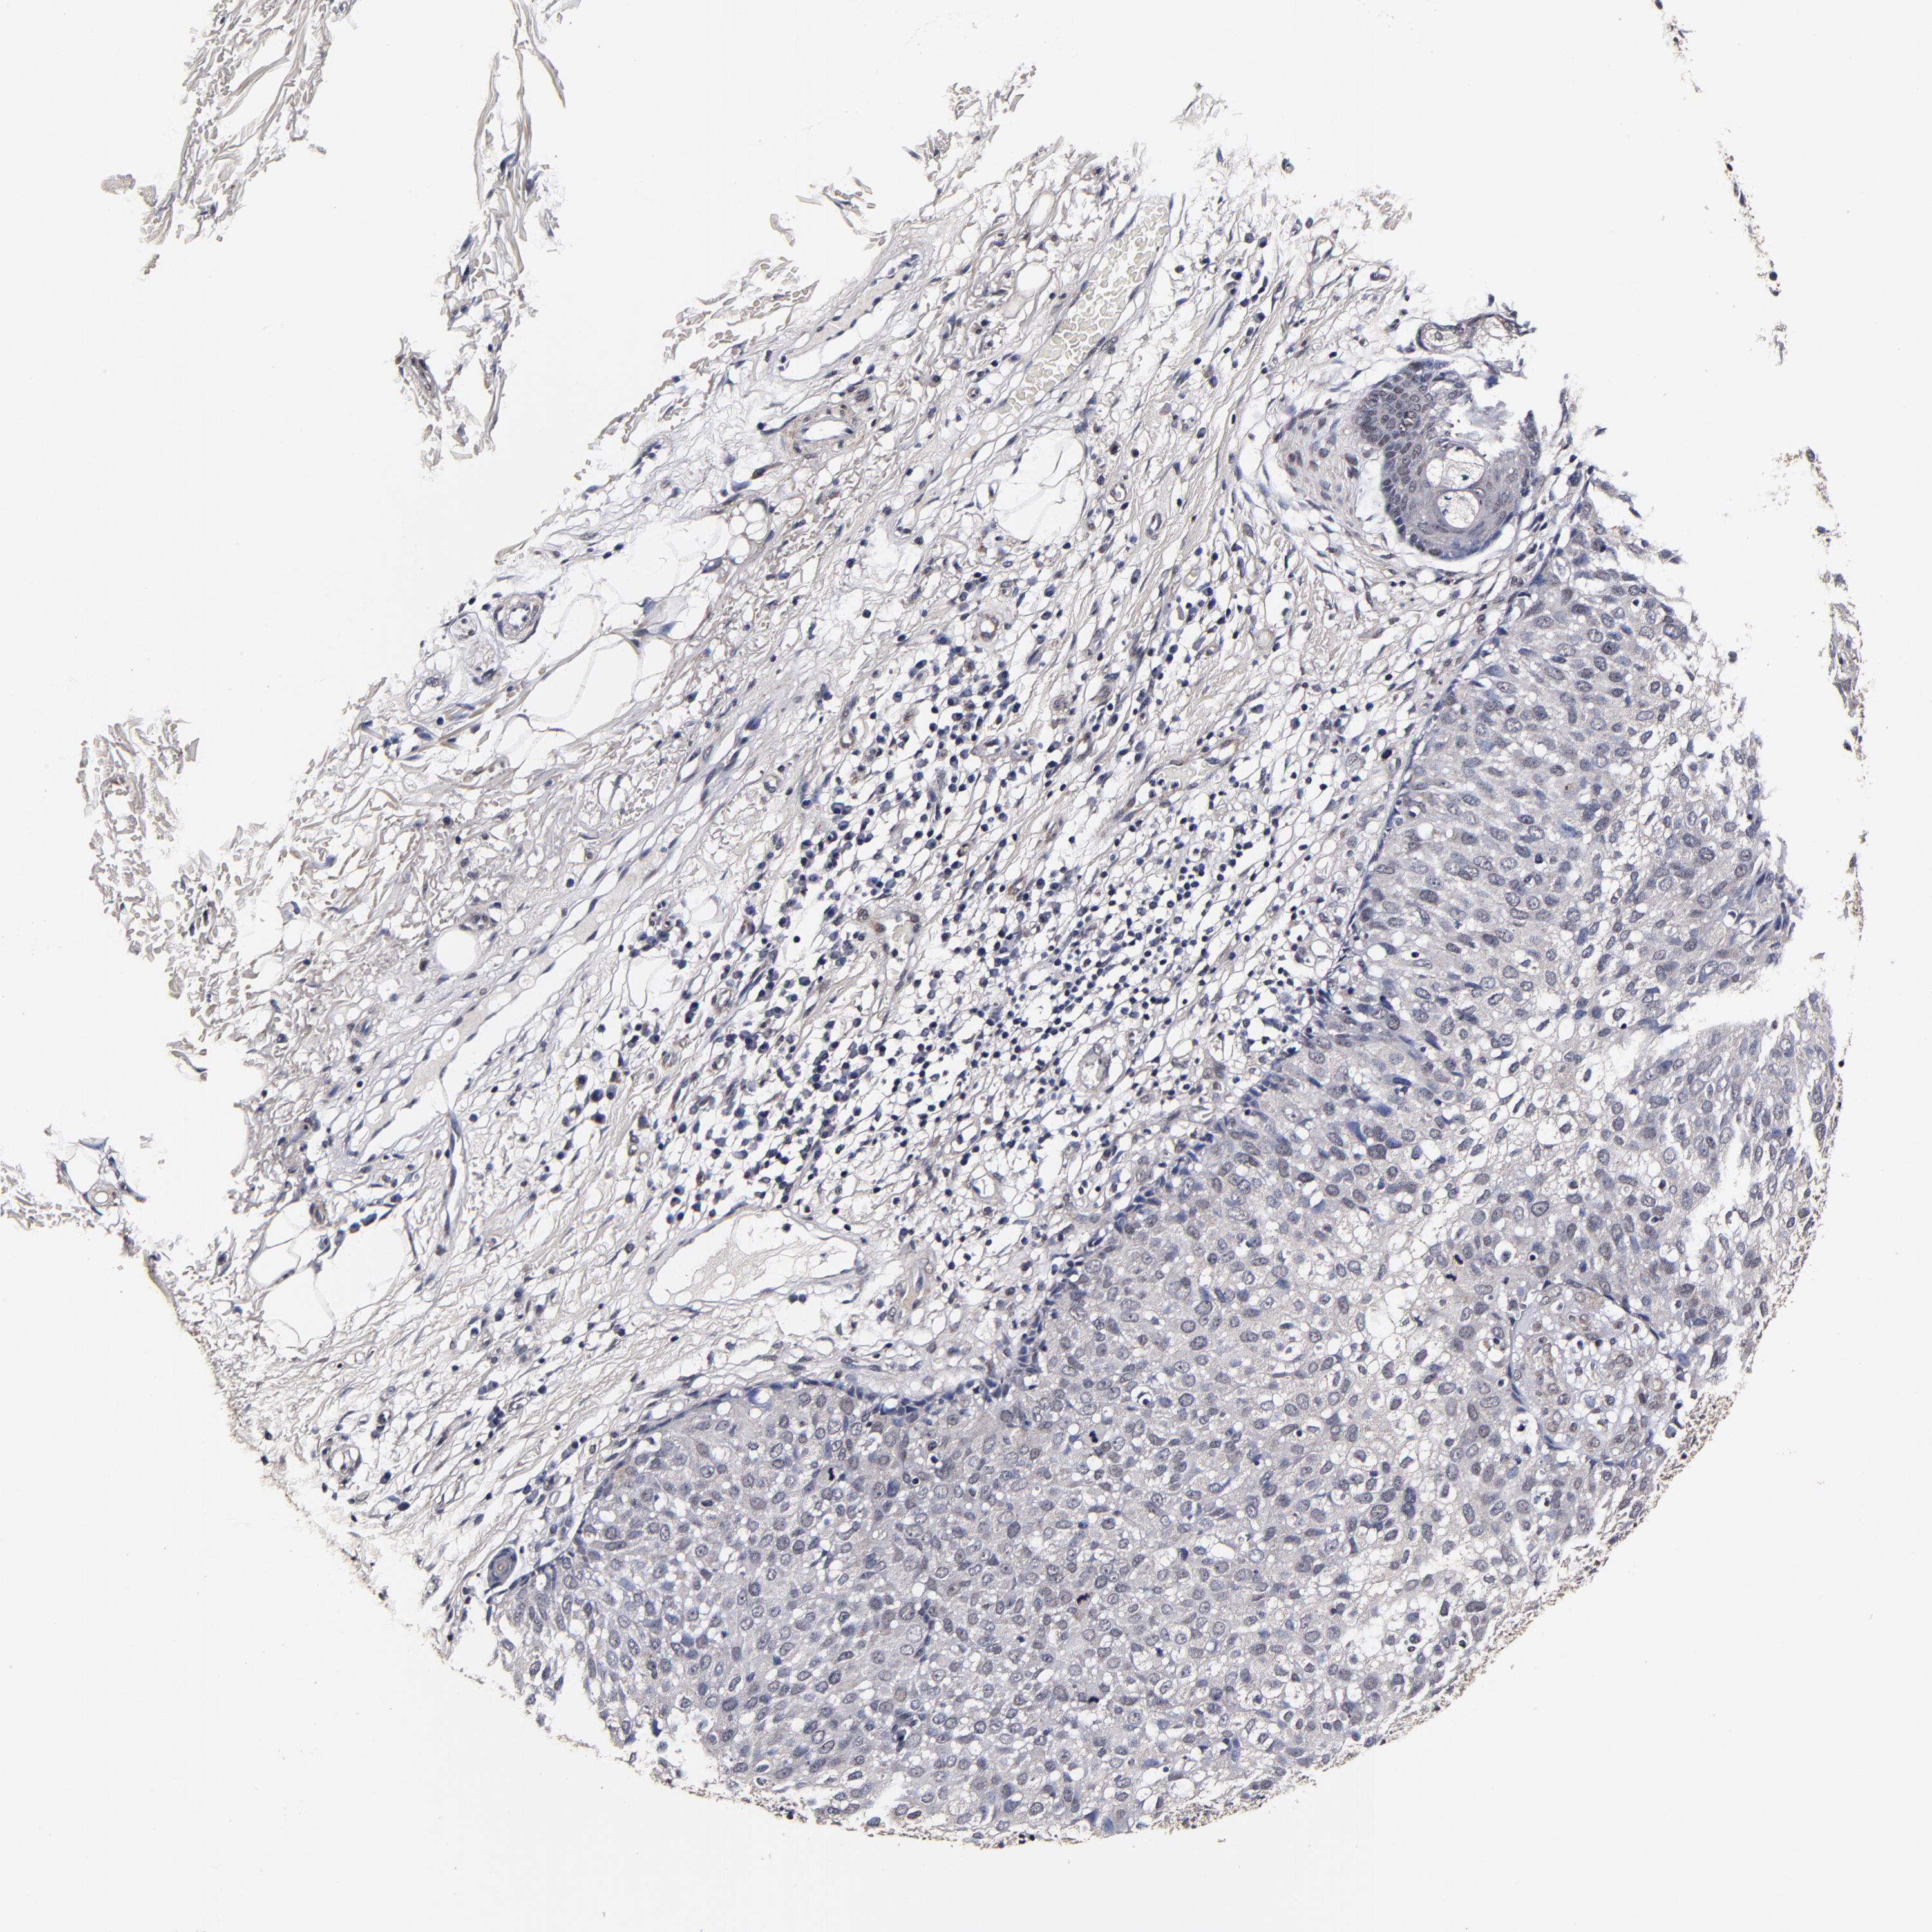

Basal cell and squamous cell cancer

SKIN CANCER - Protein expressioni

A mouse-over function shows sample information and annotation data. Click on an image to view it in a full screen mode. Samples can be filtered based on level of antibody staining by selecting one or several of the following categories: high, medium, low and not detected. The assay and annotation is described here.

Antibody stainingi

Antibody staining in the annotated cell types in the current human tissue is reported as not detected, low, medium, or high, based on conventional immunohistochemistry profiling in selected tissues. This score is based on the combination of the staining intensity and fraction of stained cells.

Each image is clickable and will lead to virtual microscopy that enables deeper exploration of all samples and also displays staining intensity scores, fraction scores and subcellular localization as well as patient and tissue information for each sample.

Antibody HPA040390

Squamous cell carcinoma, metastatic, NOS